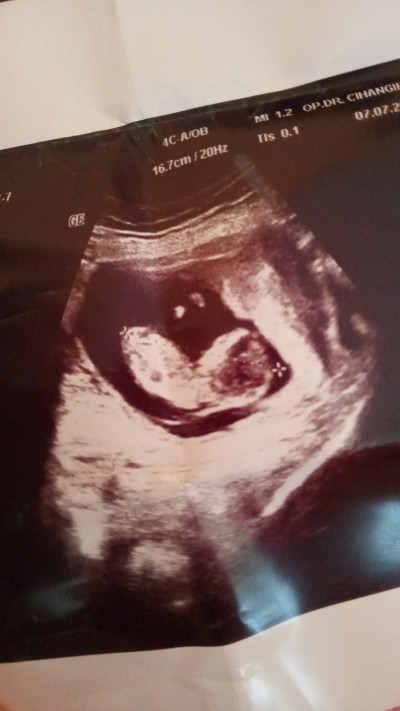

Cinsiyet yanılması olabilirmi resimli

sordu

13. Haftada özel hastanede doktor cinsiyeti erkek dedi.15. haftada devlet Hastanesi'nde başka bir doktor da erkek dedi.17. haftada devlet Hastanesi'nde farklı bı doktor kız dedi hangisine inanacagimi şaşırdım sizce nedir

17+3

Bana kız gibi geldi :) Allah sağlıkla kucağına almayı nasip etsin.